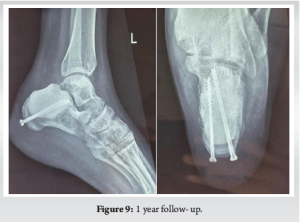

The patient was planned for extended curettage through an extended lateral approach, and the cavity filled with autologous cancellous bone graft and bone cement by the Sandwich technique (Fig. 5). The immediate post-operative X-ray image is shown in Fig. 6.

Postoperatively, the patient was kept non-weight bearing for 6 weeks, followed by partial weight bearing up to 3 months, and allowed full weight bearing then onward. The patient was followed up at 3 months (Fig. 7), 6 months (Fig. 8), and 1 year (Fig. 9) for any evidence of recurrence or articular collapse.